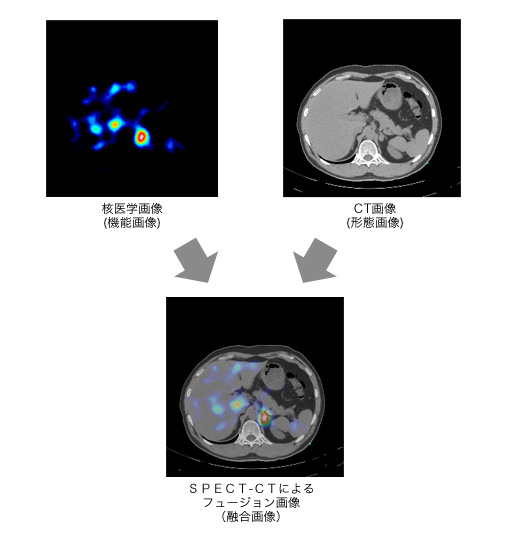

核医学検査

PHILIPS社製のPrecedence16 SPECT/CTの特徴はフルデジタルガンマカメラと高速の16列マルチスライスCT*1が一体化した"ハイブリッド装置"であることです。

診断用CTとSPECT*2を同一寝台上で行うことにより形態画像(CT画像)と機能画像(SPECT画像)の融合(重ね合せ)が可能となり、診断性能が向上します。さらにCT画像を用いた減弱(吸収)補正などを活用したAstonish 3D画像再構成*3により病変を鮮やかに描出し、疾患の程度の判定も向上します。心臓分野においては機能的心筋血流画像とCTによる減弱補正により従来の診断で判定が困難であった下壁の評価精度が向上し、更に冠状動脈のカルシウムスコアー等の算出が可能となっています。

腫瘍分野においては、特に形態画像と機能画像の融合、フュージョン画像の作成により腫瘍の位置と範囲が精度よく同定できるようになりました。

*2 SPECTとはアイソトープ検査におけるの断層画像のことです。